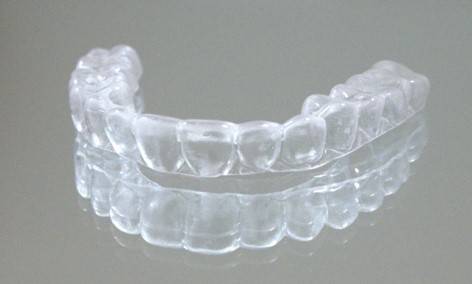

가철식 유지장치는 고정식과 달리 환자가 원할 때 언제든 붙이고 뗄 수 있는 장치다. 교정 치료가 끝난 후 보통 3개월은 식사·양치할 때를 제외하고 자는 시간까지 포함해 거의 온종일 사용해야 한다. 이후 환자 상태에 따라 잠잘 때 착용하는 등 사용 시간을 줄일 수도 있다.

가철식 유지장치를 착용한 채로 식사하면 장치가 망가질 우려가 있어 장치를 빼두는 게 좋다. 그러나 외식할 때 남들의 시선이 부담스러워 빼놓은 장치를 휴지로 감싸둔 채 식사하다가 깜빡하고 두고 가, 장치를 잃어버리는 경우가 종종 있다. 따라서 장치에 불필요한 외력이 가해지는 것을 막고, 분실도 방지하기 위해 장치를 사용하지 않는 동안에는 전용 통에 넣어 보관하는 게 좋다.

가철식 유지장치의 세척에 대해 안정섭 교수는 "장치를 적절히 세척하지 않을 경우 가철식 유지장치에도 치석이 붙을 수 있어, 칫솔을 이용해 장치를 주기적으로 닦아주는 것을 권장한다"라며, "치약을 사용해 장치를 닦으면 장치 표면이 마모되기 때문에 양치질하고 칫솔에서 치약을 헹궈 낸 뒤 가철식 유지장치를 닦아줄 것을 추천한다"라고 설명했다.

장치를 소독하기 위해 뜨거운 물에 삶아도 될까. 안 교수는 "삶으면 장치의 플라스틱 부분이 변형해 장치를 사용할 수 없게 된다"며 "시중에 교정용 유지장치 소독을 위한 세정제가 판매되는데, 장치 디자인에 따라 특정 세정제를 사용하면 장치의 철사 용접 부분이 망가지는 경우도 있어 사용 전 치과의사에게 문의하는 게 안전하다"고 답변했다.